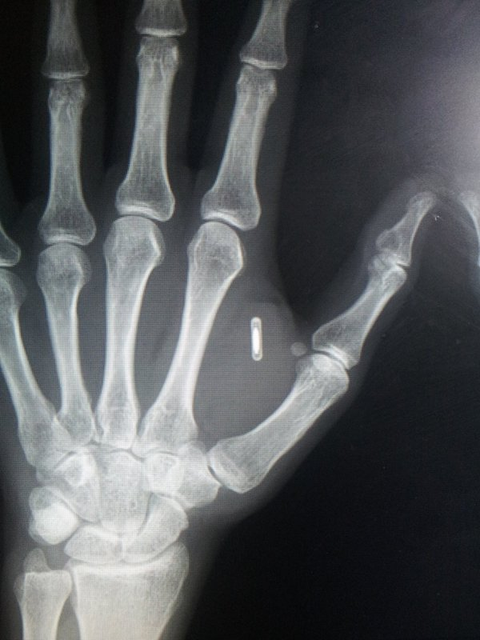

미국에서 첫번째 법정 승소자- 제임스월버트 (James Walbert)사례

치과에서 임플란트 시술후 마인드컨트롤전파무기피해가 시작되어서

임플란트를 뽑아 속을 보니 RFID칩이 발견되어 법정승소하는데 ~

결정적인 증거로 작용되었다!